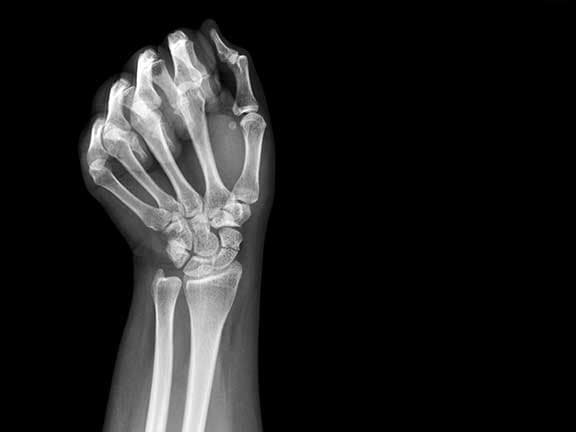

Skafoid Kırığı Belirtileri

Skafoid kemiği, el kemikleri ve ön kol arasındaki bağlantıyı sağlayan sekiz karpal kemikten biridir. Bu kemik, anatomik...